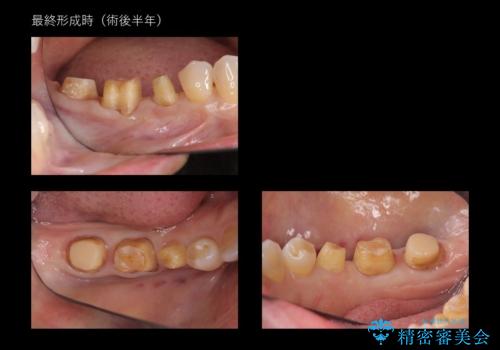

奥歯の高さがない 歯周外科で解決

- 右下奥歯(7番)の高さがなく、かぶせ物(クラウン)にするためにあらかじめ歯周外科手術を行いました。(クラウンレングスニング)

右下5番は歯ぐき付近までWSD(くさび状欠損)で削れていたため、患者様と相談してクラウンにしました。その際、削れていたのが歯肉縁下に及んでいたため、一緒に手術範囲に含めました。

特に根尖に症状がなかったため、右下7番の根管治療はやり直していません。

歯の高さを出すとかぶせ物(クラウン)がはずれにくくなります。

今回は右下7番が神経のない歯だったため、クラウンにして割れにくくしています。